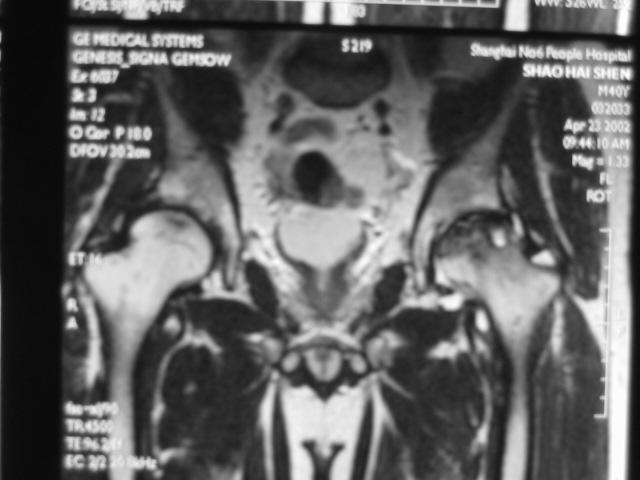

MRI诊断

Ⅲ期

髋关节间隙正常,无狭窄。

股骨头表面毛糙、开始变形。

软骨下皮质出现骨折,进一步发展出现轻微塌陷、阶梯状改变。

新月体形成:新月体代表无法修复的坏死骨发生引力性骨折,在T1W上为带状低信号区,T2W上,由于细胞内液渗出或关节液充填骨折线而呈高信号

股骨头表面软骨的完整性受到一定影响。